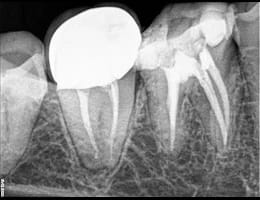

Permanent Restoration:

After the root canal is completed, the temporary filling is removed, and a permanent restoration, such as a crown, is placed to protect and restore the tooth’s function.